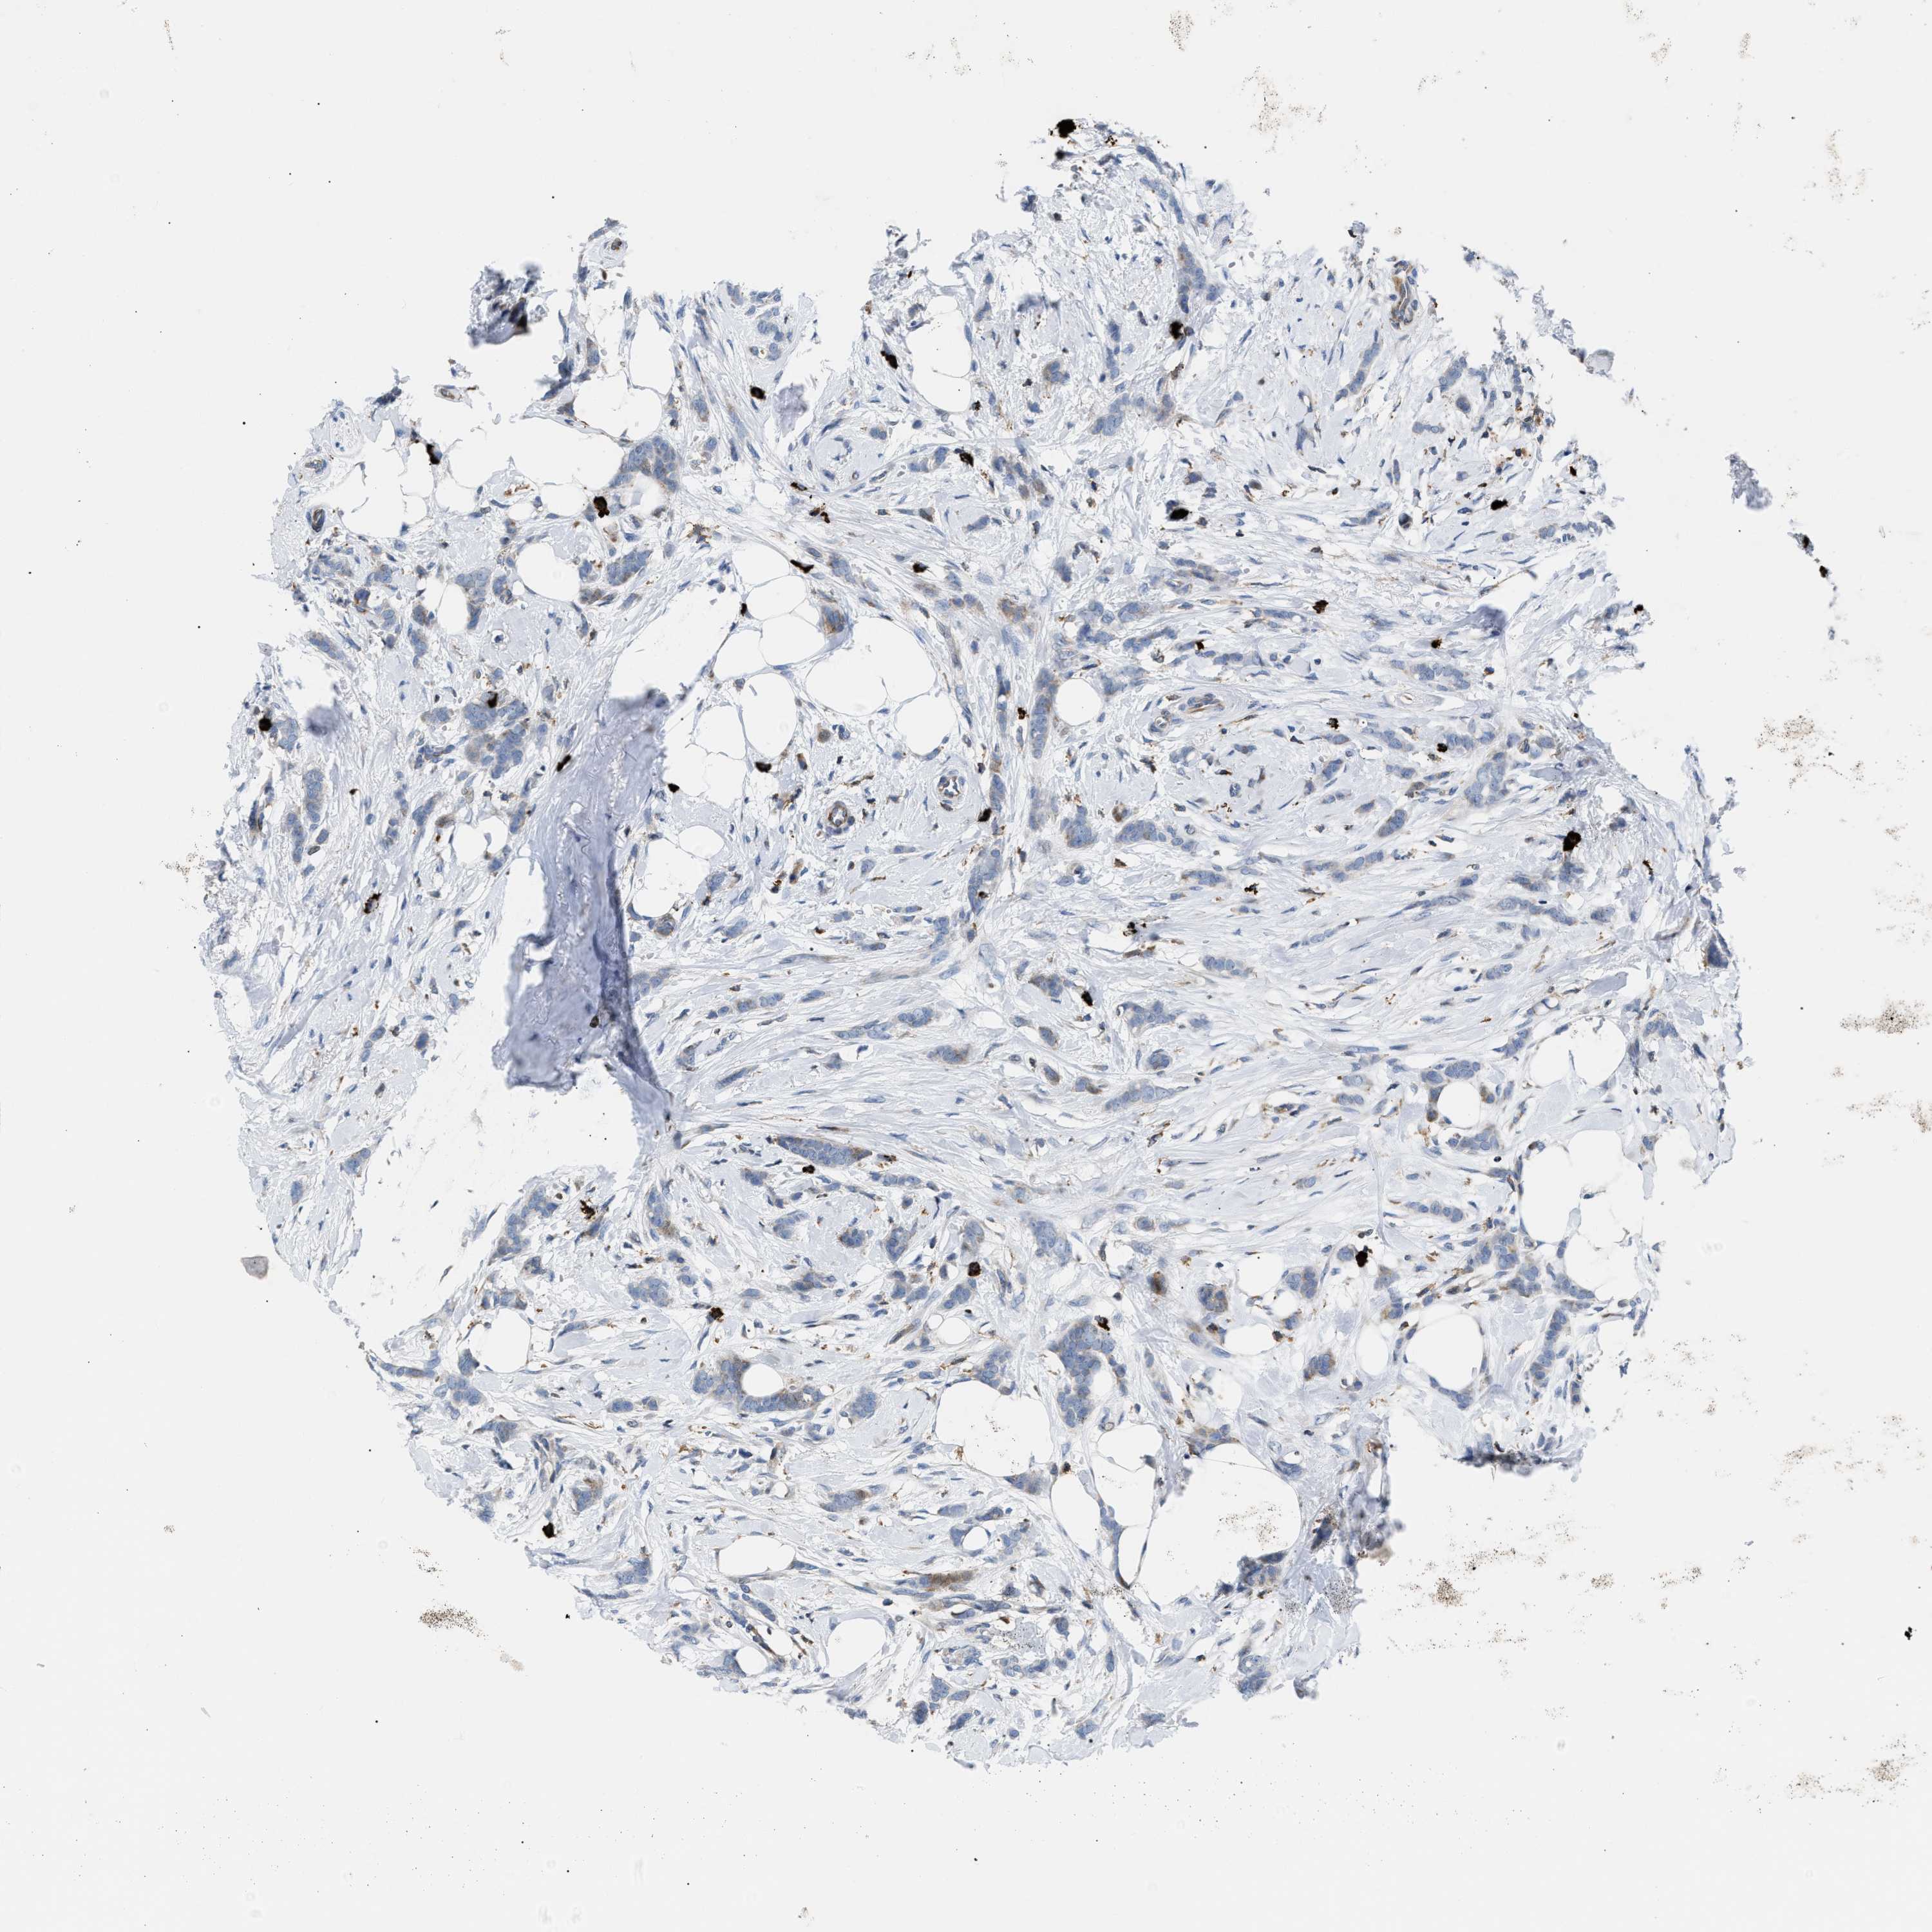

CANCER BREAST CANCER Show tissue menu

BRCA TCGA BRCA VALIDATION PROTEIN EXPRESSION

Breast cancer

Human cancer